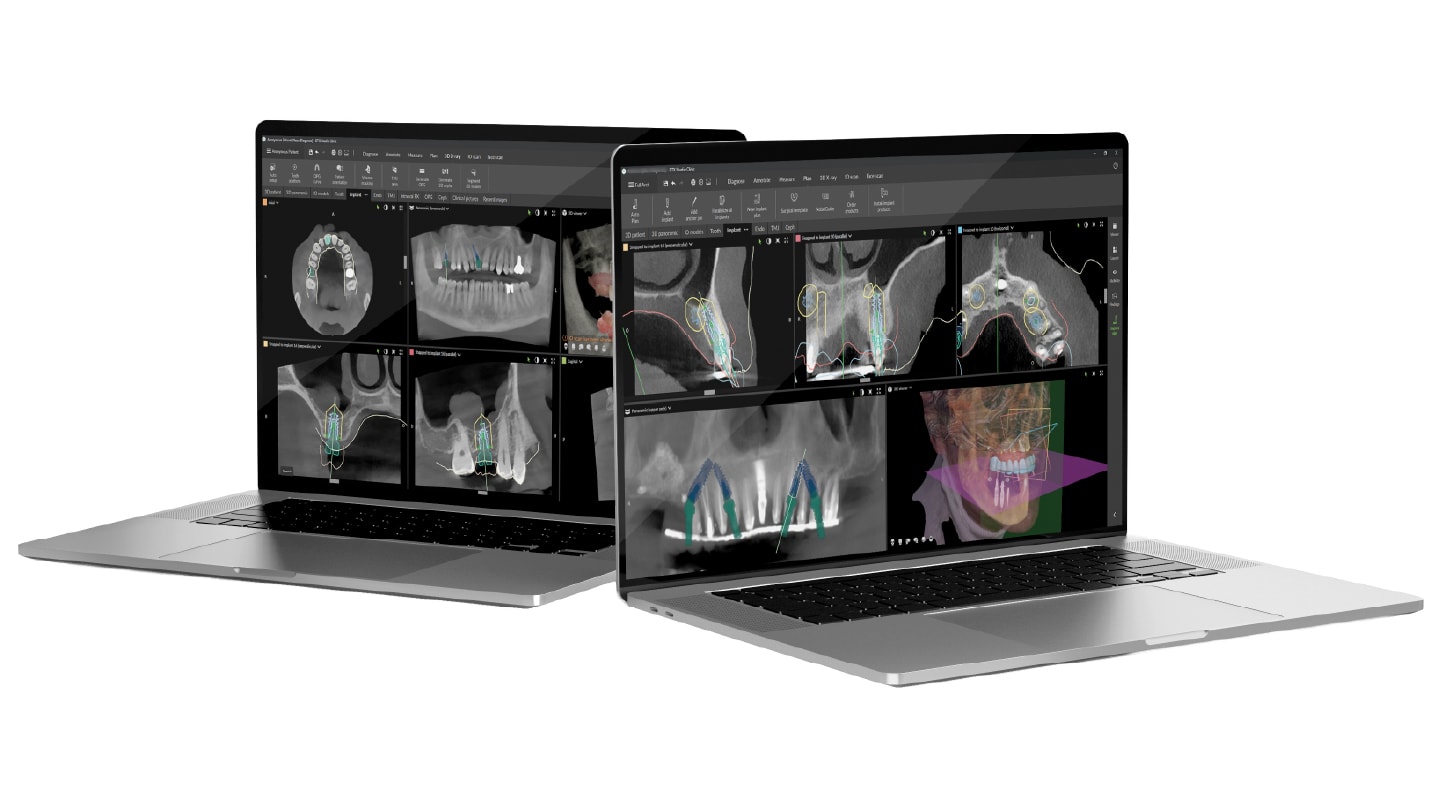

Today, Dr. Arora’s digital workflow allows him to provide a fixed temporary restoration within minutes of implant placement. Central to that process is digital treatment planning using DTX Studio™ Clinic software. At the initial consultation, patient records—including photographs, CBCT scans, facial scans, and intraoral scans—are integrated into the platform to create what he describes as a virtual patient. “You take all these files and with the help of DTX, you make a virtual patient and based on that you decide where exactly you want to place the implant,” he says.

This planning phase is critical because immediate temporization requires adequate primary stability. According to Dr. Arora, achieving approximately 5 mm of implant engagement in natural bone provides the stability necessary to proceed with immediate loading. By planning implant size, position, and prosthetic design in advance, the surgical placement can follow the digital plan precisely. “Because the planning has been done to the teeth, we are able to send all the data files right after the placement to a lab,” he explains.